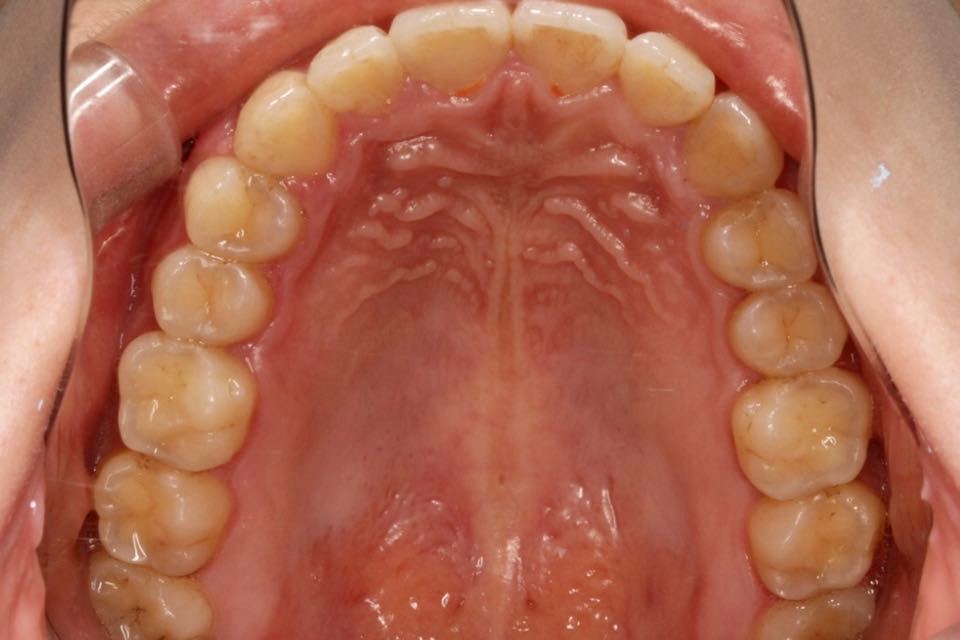

矫正后口内照:

治疗改善:关闭散隙,调整中线。

目前阶段:全口牙齿排列整齐,中线居中。前牙覆合覆盖正常,尖磨牙关系达I类咬合关系。总疗程约18个月。